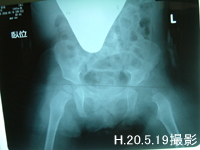

さて今週の月曜日に撮ったレントゲンの結果ですが8ミリ引けていて基準値に達しました。やったぁー!来週の月曜日から第二段階に入る事が決まり少し先が見えてきた。早く退院したいー!